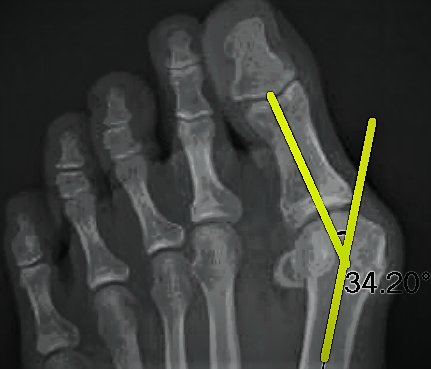

This is Andriany’s initial x-ray, as you can see below her initial bunion angle was 34 degrees which is classified as an advanced bunion, where a normal angle is between 12-15 degrees.

As you can see a significant change of 14 degrees has been achieved! With minimal ongoing treatment we would expect the toe to further straighten till it’s anatomically straight.